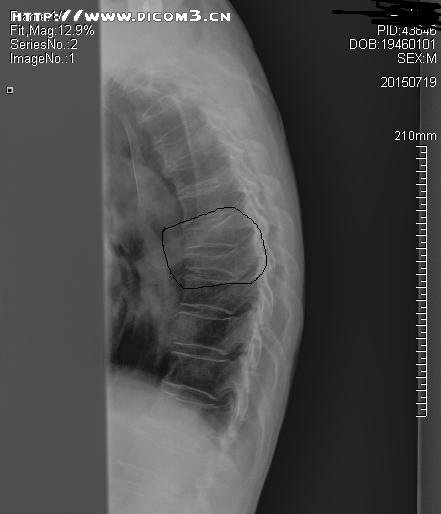

来诊时,患者已经12天未排大便,查体:腹部膨隆,脐上压痛,肠鸣音稍亢进,舌红苔黄厚腻,脉弦滑,见患者进诊室时就一直含胸驼背,追问患者病情,自述其后背部隐痛不适,不敢直腰,进一步扩大查体范围,查脊柱发现,胸8、9棘突尖、椎体两侧旁压痛叩击痛明显,建议患者行胸椎正侧位X片检查,患者满脸狐疑,“明明是肚子不好,拍什么胸椎片啊”,还好,之前攒了点人品,这时起了作用,患者虽然疑心重重,但最终还是听从了我的建议,拍片检查示:胸8.9压缩性骨折,再追问既往病史,患者无明显外伤史,但此前曾长期口服激素类药物,病情叙述到此打住,问题来了,患者好好的怎么就骨折了呢?即便有骨折,又与大便不通又有什么关系呢?

胸椎侧位片(标识处为压缩性骨折部位)